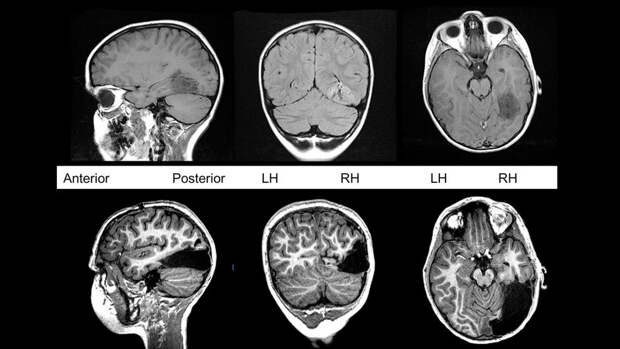

Так, у человека с обычной шизофренией наблюдается меньше мозговой ткани, чем у здорового человека. Новый же тип не влияет на объемы серого вещества, они остаются схожими с нормальным мозгом.

Заключение было сделано на основе анализа мозга у 300 пациентов с данным заболеванием.